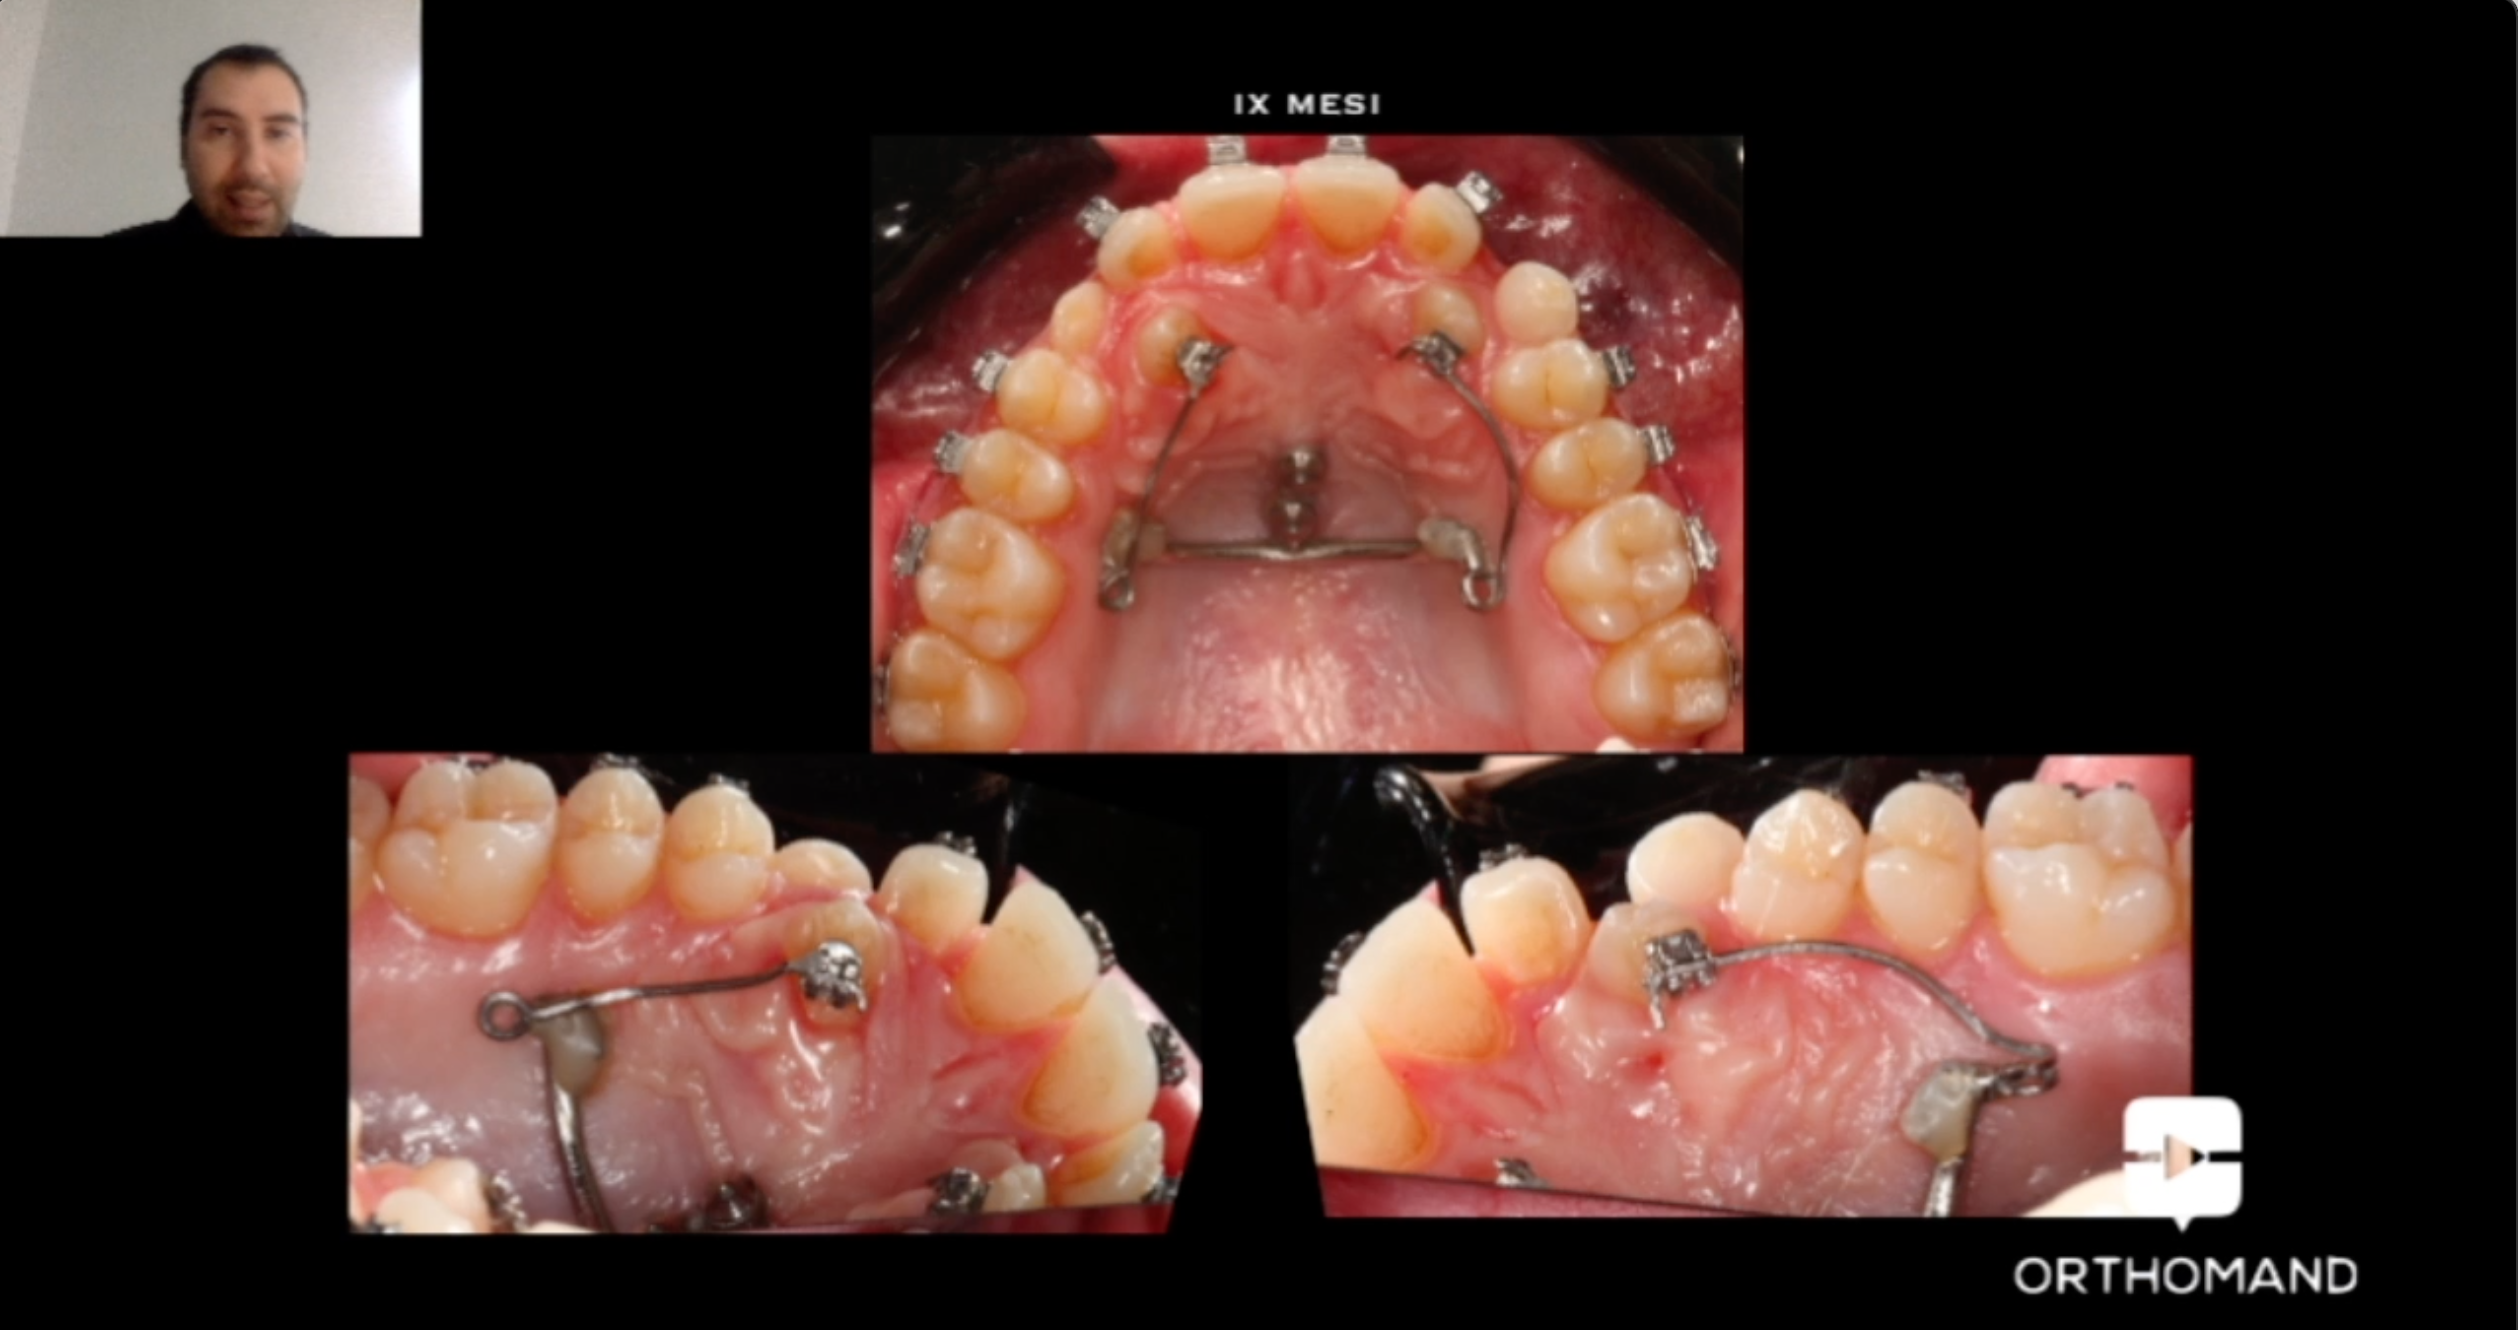

La disinclusione del canino palatale rappresenta una vera sfida per l’ortodontista. Molte tecniche classicamente utilizzate mostrano rischi e limiti di predicibilità clinica. La finalità del corso è esporre un nuovo approccio di trattamento all’inclusione palatale del canino. Attraverso la scelta di ancoraggi scheletrici e di meccaniche segmentate è possibile trattare in maniera predicibile, efficiente ed efficace tale rilevante problematica ortodontica riducendo molti classici effetti avversi, senza alcun impatto estetico e di compliance del paziente. Il workflow digitale fornisce, inoltre, un valore aggiunto in termini di pianificazione dell’ancoraggio scheletrico, di piena individualizzazione del dispositivo ortodontico e di aiuto nella gestione segmentata della tecnica di disinclusione.

Estratti dal corso